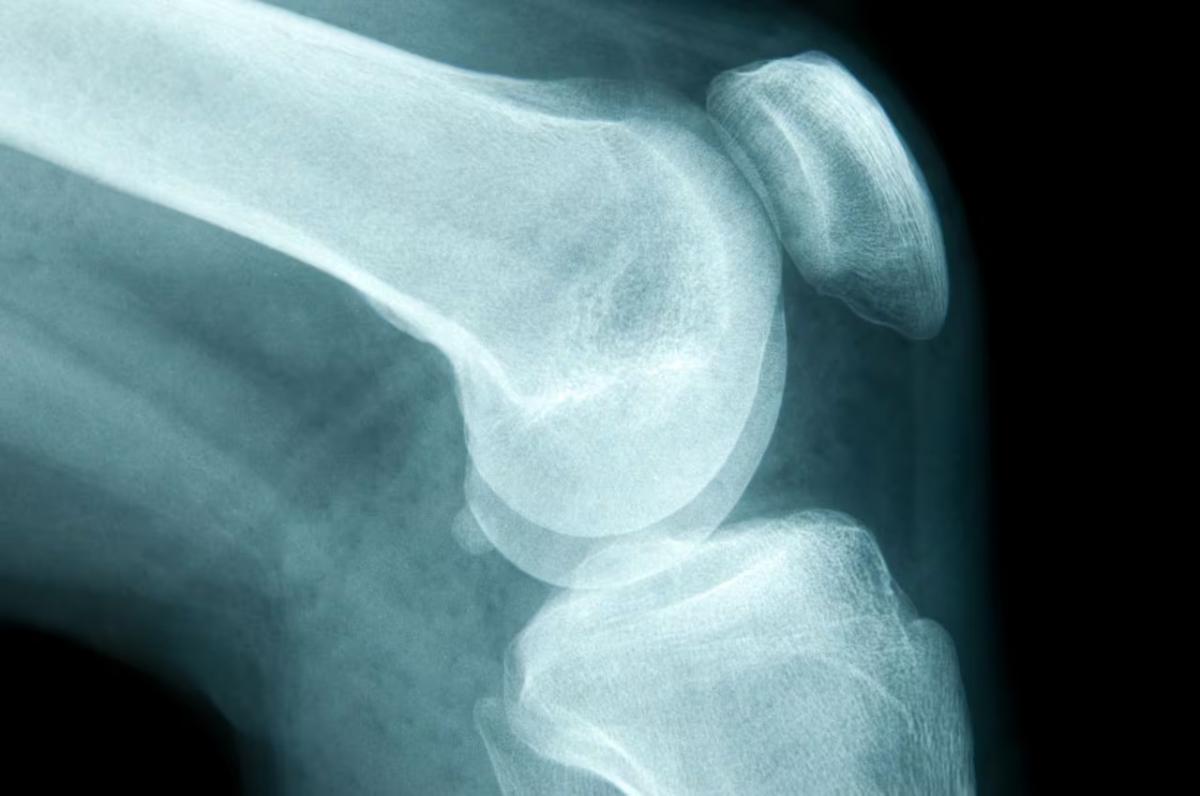

- Osteosarcoma: generalmente, se desarrolla entre los 10 y 19 años de edad y ocurre más comúnmente en la rodilla o en la parte superior del brazo.